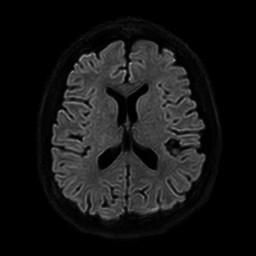

뇌 후두피질위축 봐주시면 감사하겠습니다(mri)

요즘 눈이랑 정신이 좀 이상해서 뇌mri를 찍었는데 이렇게 나오네요.

• 2번 째 사진

정확한 것은 정식 판독을 받아보아야 알 수 있겠습니다만, 개인적인 경험을 토대로 보았을 때에는 위축이 심하다고 보기에는 무리가 있어 보입니다. 뇌실이 비정상적으로 커져 보이지도 않고 뇌의 태두리가 두개골에서 많이 떨어져 있지도 않은 것이, 해당 사진들만 보아서는 위축이 심하고 치매를 의심하여야 한다 어떻다 판단을 내리기는 어려울 것으로 사료됩니다.